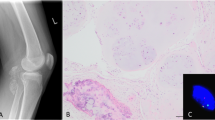

In 10/14 cases of OA synovia and in the two cases of normal synovia, expression of HMGIC was detected at the RNA level (Table 1; Fig. 1). Because some of the cases displayed low expression, the expression experiments were performed several times in order to confirm the positive cases. No attempt to quantify the expression was made.

The picture shows some of the cases analyzed for expression of HMGIC at the RNA level. cDNAs from OA-affected and normal synovial biopsies were subjected to PCR with HMGIC-specific primers, resulting in a 192-bp fragment. As an internal standard, amplification with ACTB-specific primers for a 626-bp fragment was simultaneously performed. Lane 1: Case 26 (OA-affected synovia); Lane 2: Case 24 (OA); Lane 3: Case 25 (OA); Lane 4: Case 29 (OA); Lane 5: Case 34 (OA); Lane 6: Case 40 (normal synovia); Lane 7: Case 41 (normal synovia); Lane 8: normal adipose tissue; Lane 9: cultured amniocytes.